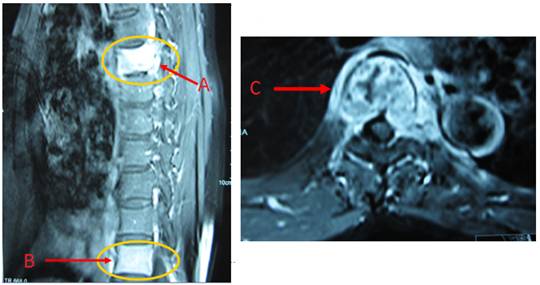

Kết quả chụp cộng hưởng từ (MRI) cột sống tại Bệnh viện Xây dựng như sau:

(A,B: Tổn thương thân đốt sống D7 và D12 trên hình ảnh cắt dọc

C: Tổn thương đốt sống có xâm lấn tủy sống trên hình ảnh cắt ngang)